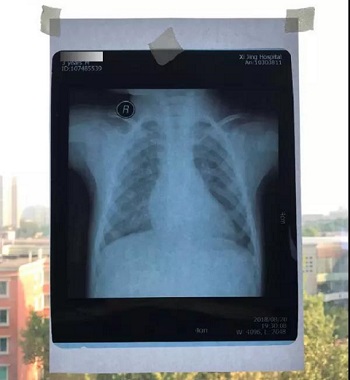

把片子直接贴在窗户玻璃上拍,窗户外面的风景透过片子拍入了照片上,图片的下半部分,可以隐约看到窗户外面的建筑,影响医生阅片,不能获取有价值的磁共振信息。

七、将白纸或白布贴于窗户玻璃上,然后将X光片或磁共振或CT片子贴于白纸或白布上。如果用的是电脑显示器翻拍片子,则按照上一条方法将显示屏变白色后,将片子贴于显示器上进行拍照。拍照时一定要正对着片子拍,注意横平竖直,拍端正了,不要拍歪斜了。

拍摄时,必须要对着片子上的文字对焦, 方向正确,将文字拍摄得清晰可视,保证放大图片后文字依然清晰可见(如下图),尽可能多的保留片子上的信息。